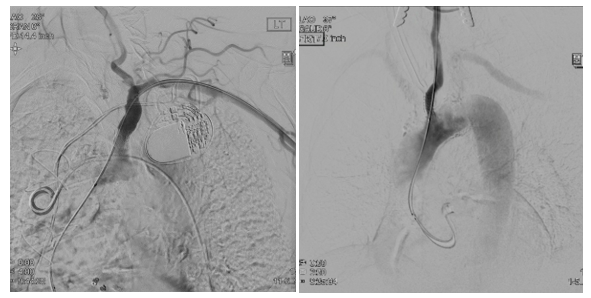

An 82-year-old man with a medical history of coronary artery disease (CAD) status post coronary artery bypass grafting and percutaneous intervention (PCI), peripheral arterial disease (PAD), hypertension, sick sinus syndrome with a permanent pacemaker, and paroxysmal atrial fibrillation presented with more than 6 months of lightheadedness and loss of balance. A computed tomography (CT) angiogram revealed 70% to 75% stenosis at the proximal segment of the left internal carotid artery (ICA) at bifurcation and the ostial common carotid artery (CCA), 99% subclavian artery stenosis, and a heavily calcified type 3 aortic arch (Figure 1). Given the ostial location, degree of calcification, and severe angulation related to a type 3 arch, a retrograde approach was favored over the traditional transfemoral route due to concerns about safe catheter and wire maneuverability. Treatment was planned with a hybrid approach, where a vascular surgeon and interventional cardiologist worked in tandem. In a multistage procedure, the patient first underwent stenting of a left sub-totally occluded subclavian artery via a transfemoral approach. Three weeks later, he returned for a hybrid procedure. Under general anesthesia, the vascular surgeon first performed the carotid cutdown. Neuroprotection was achieved using distal clamping of the ICA and external carotid artery. Following standard heparinization, a short 6Fr sheath was placed in a retrograde manner over a 0.35” Supra Core wire (Abbott) (Figure 2). Afterwards, the patient underwent a typical carotid endarterectomy (CEA) by CT surgery.

The second patient was a 72-year-old-woman with medical history of CAD status post PCI, PAD, and chronic obstructive pulmonary disease who presented with 6 months of dizziness, presyncope, and right arm numbness. A CT angiogram revealed 75% to 80% ostial left CCA stenosis, left ICA stenosis, and critical stenosis of the brachiocephalic artery, as well as a type 2 aortic arch with severe calcification at the origin of the great vessels (Figure 1). Similar to the first patient, a hybrid approach with retrograde stenting of the left CCA was recommended due to the extent of calcification, challenging vascular anatomy, and concurrent ICA stenosis. After a combined effort from interventional cardiology and CT surgery, the patient had carotid cutdown and neuroprotection, identical to the first patient, with successful placement of an 8- x 19-mm Omni Link stent (Abbott) into the ostial left CCA followed by a successful endarterectomy (Figure 2). A month after the procedure, she underwent a second procedure to intervene on the brachiocephalic artery stenosis with successful placement of a 9- x 19-mm Omni-link stent and right ICA CEA.